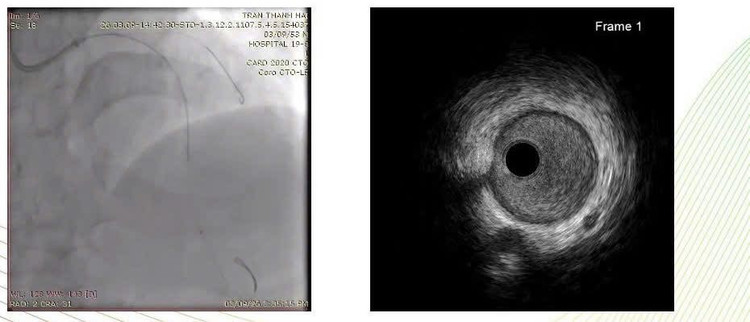

Kết quả chụp động mạch vành cho thấy tổn thương vôi hóa rất nặng, hẹp khít nhiều đoạn của hệ động mạch vành, với SYNTAX score 26.

Đánh giá tổn thương bằng IVUS, Siêu âm trong lòng mạch (IVUS) cho thấy: Vôi hóa gần như chu vi toàn bộ lòng mạch; Lòng mạch hẹp khít.

Đây là dạng tổn thương đặc biệt khó trong can thiệp mạch vành, vì stent rất khó nở nếu không xử lý tốt mảng vôi hóa trước.